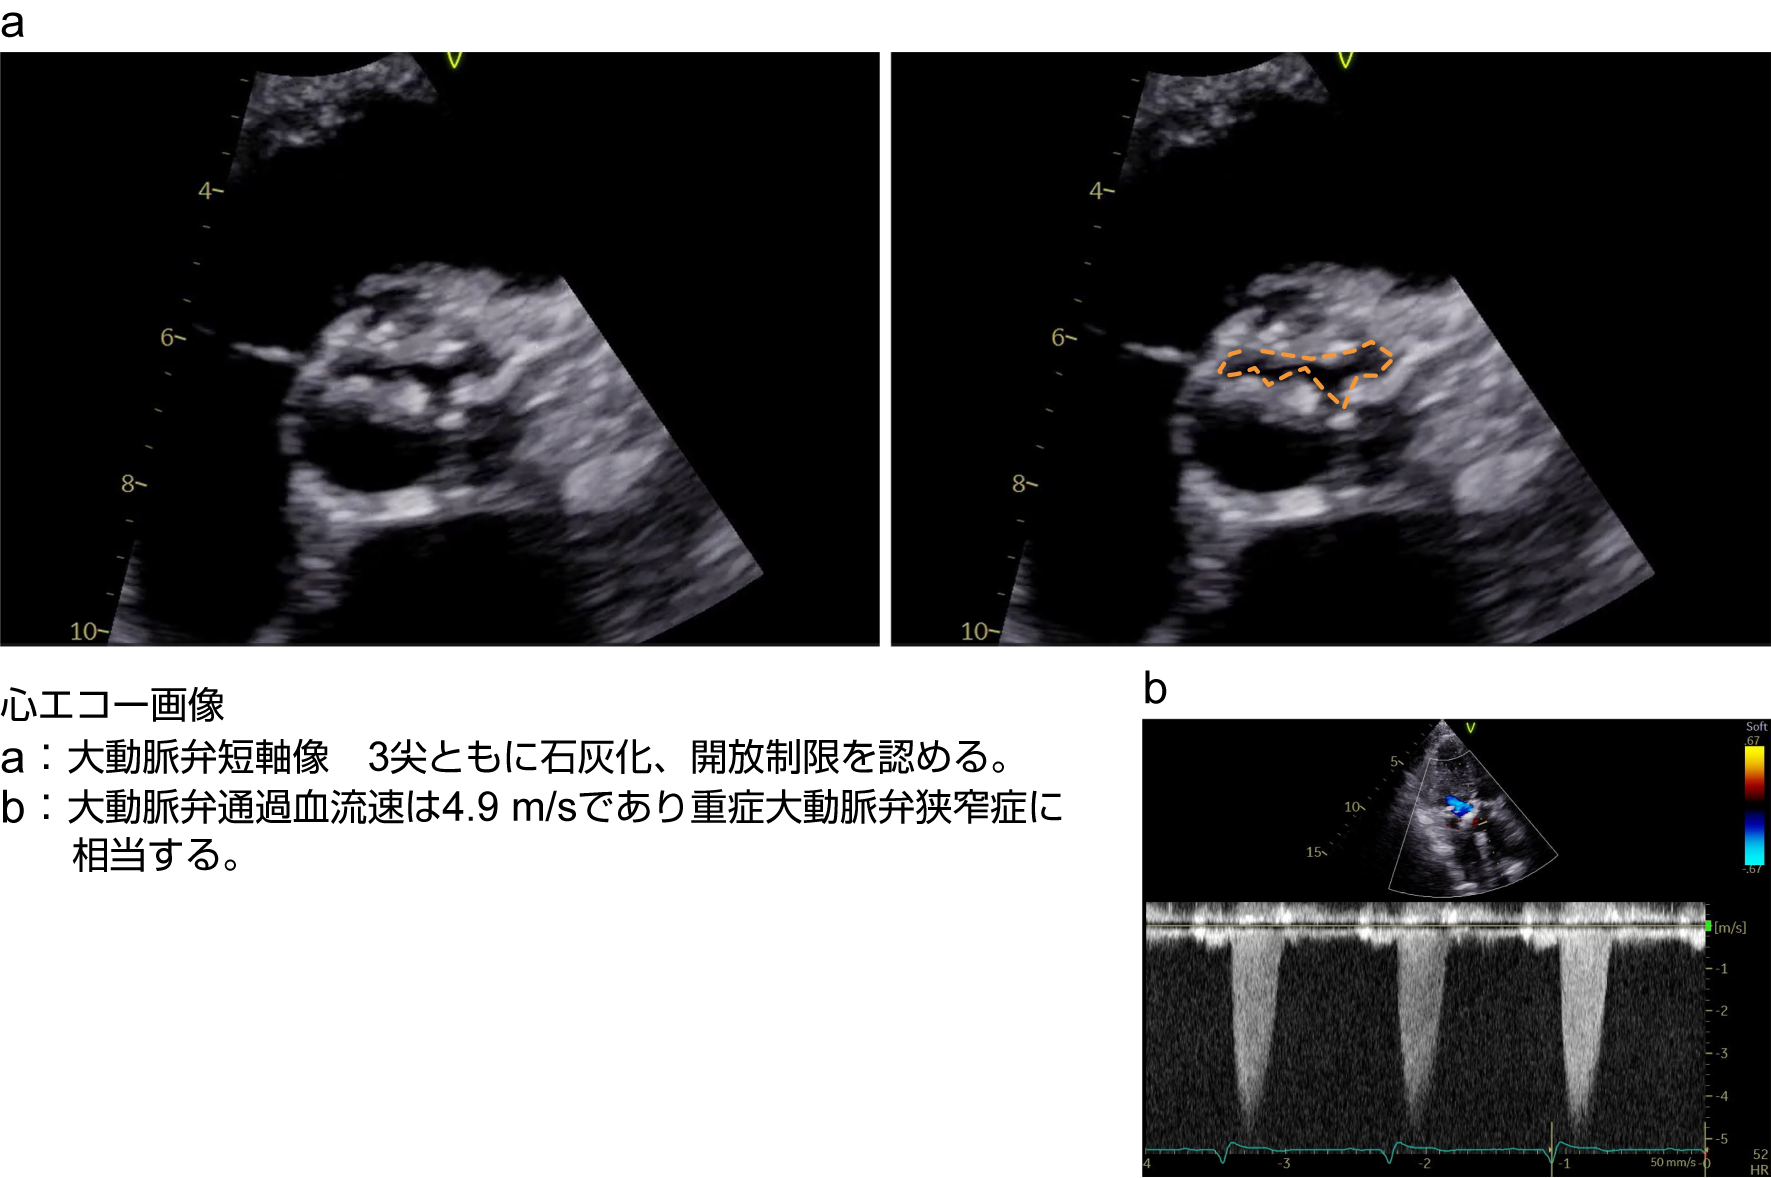

重症ASの経胸壁心エコー(TTE)

出典

img

1: 著者提供